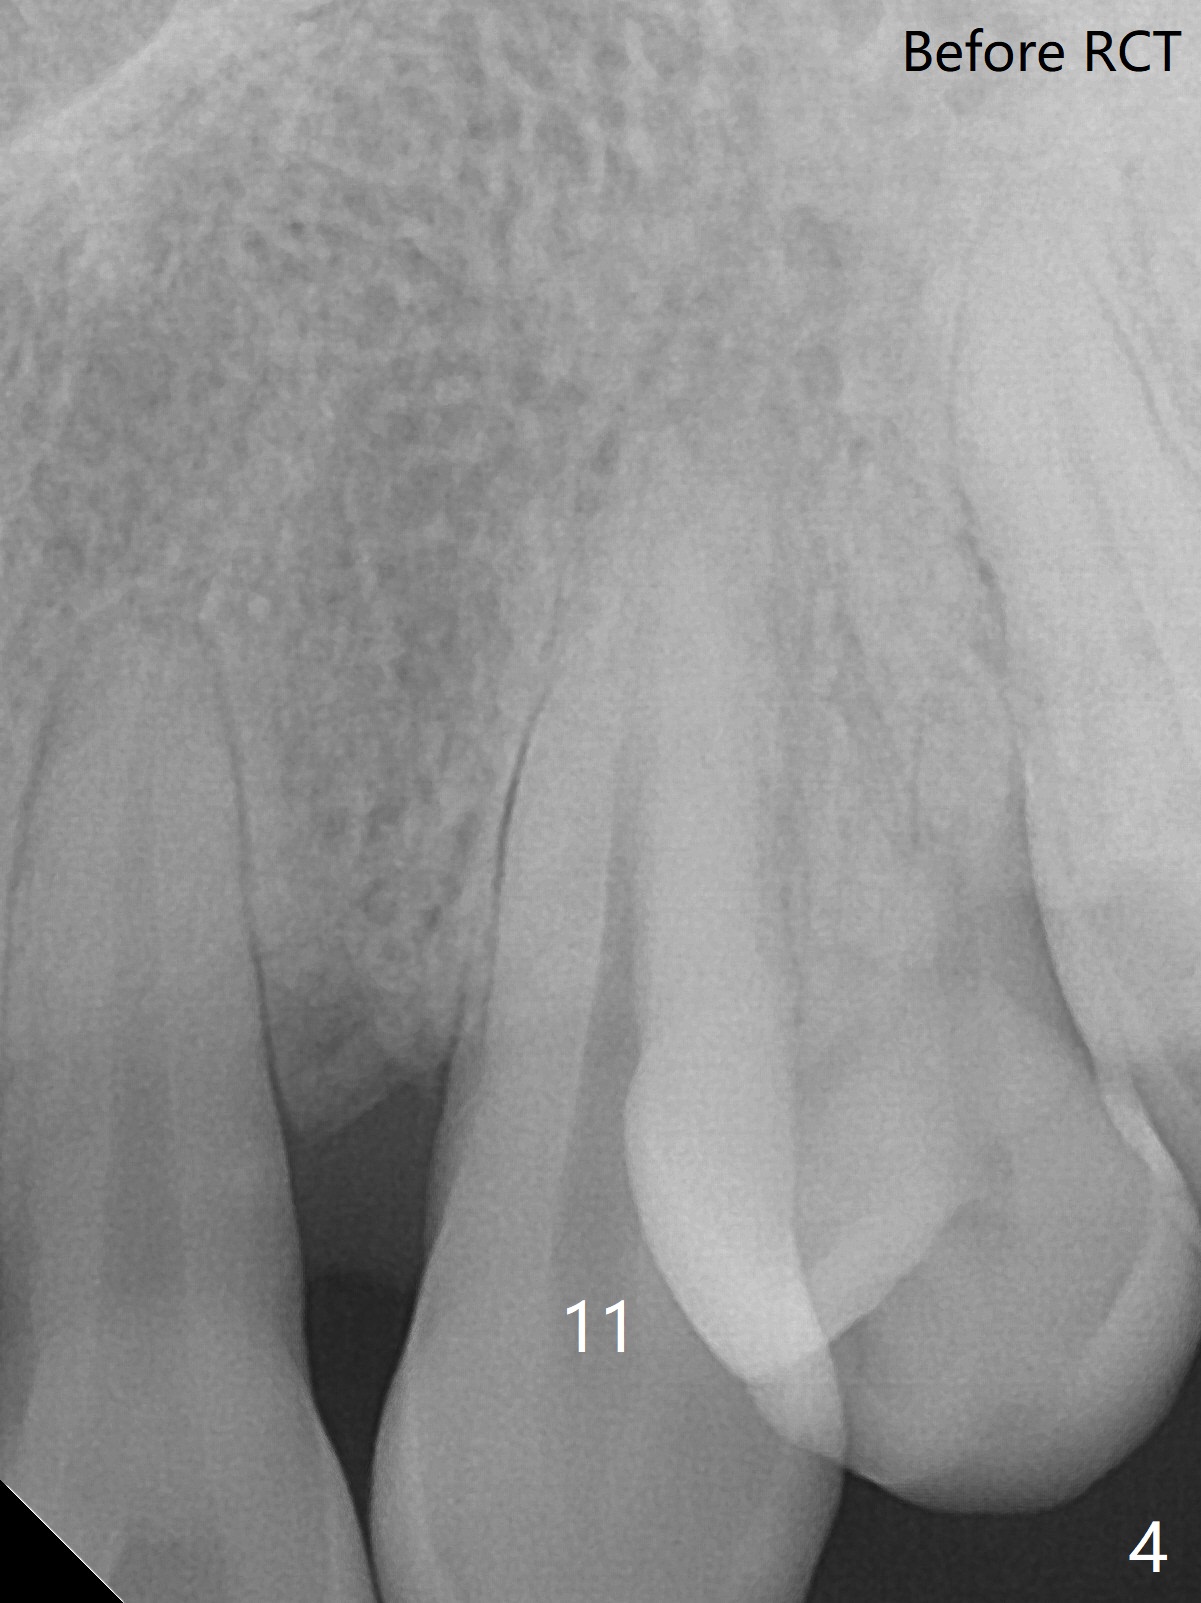

A 45-year-old man had severe malocclusion and chose non-extraction orthodontic treatment (Fig.1 (2012)). Five years later, the tooth #11 discolors (Fig.3, as compared to #6 in Fig.2). Immediately after RCT (Fig.4,5), the affected tooth has sudden change in shade (Fig.6). Two weeks later there is rebound in shade (Fig.7). The latter improves after two rounds of chair-side internal bleaching with 35% Hydrogen Peroxide for 20 minutes and build-up with the lightest shade composite (Fig.8). For optimum, place the bleach gel in the pulpal chamber and close the access with Cavit for a few days. In fact the latter is unnecessary. The treated tooth looks as normal as the tooth on the other side 1 year 10 months post whitening (Fig.9). PARL reduces 3 years post RCT (Fig.10 <, as compared to Fig.5).